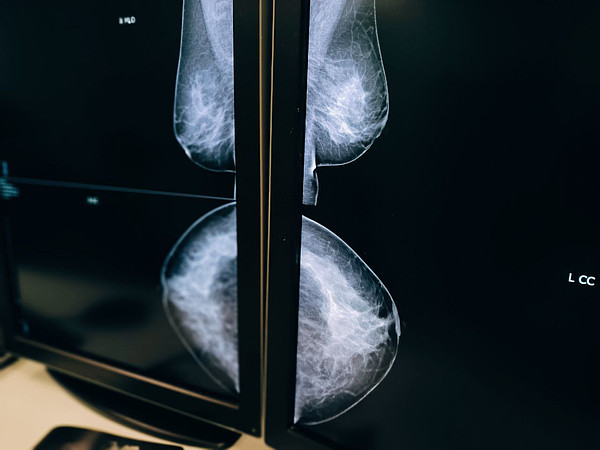

photo_7_2025-10-20_15-49-03.